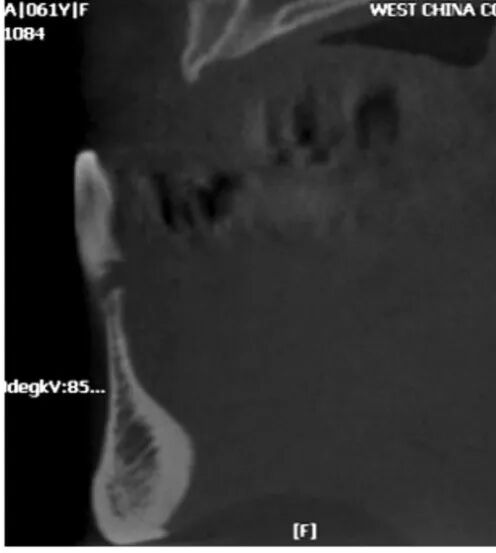

图7 术前矢状位

CBCT片显示牙槽骨密度低,正在愈合中

图8 术后CBCT片矢状位

显示种植体植入5个月后2期修复前的状况